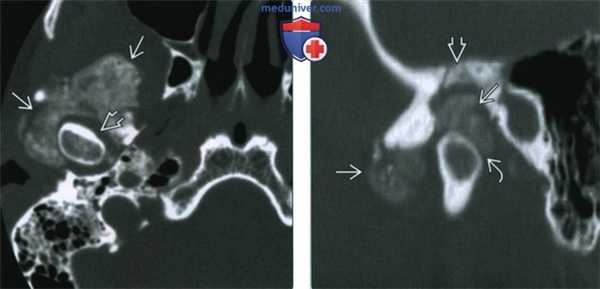

(Слева) На аксиальной КТ основания черепа в костном окне у пациента с болезнью накопления КПФД вокруг головки и шейки мыщелка нижней челюсти справа определяются многочисленные включения с плотностью кальция. Обратите внимание на сохранное суаавное пространство вокруг мыщелка.

(Справа) На сагиттальной реформатированной КТ в костном окне у этого же пациента лучше видны кальцинаты в области ВНЧС. Обратите внимание на деминерализацию и эрозию крыши суставной ямки (дефект средней черепной ямки). Нижний отдел суставного пространства прослеживается, но выглядит сдавленным. (Слева) На корональной КТ в костном окне у этого же пациента определяются кальцинаты с наружной и внутренней стороны от мыщелка со склерозом и эрозией височного компонента ВНЧС.

(Справа) На корональной КТ в костном окне у этого же пациента с наружной стороны от мыщелка визуализируются кальцинаты внизу доходящие до уровня шейки мыщелка. Определяется обширная эрозия суставной ямки (дефект средней черепной ямки справа).

(Слева) При аксиальной КТ в костном окне, полученной на уровне основания черепа, визуализируется обширный обызвествленный участок вокруг мыщелка нижней челюсти справа. Обратите внимание на отсутствие патологических изменений со стороны суставного пространства вокруг мыщелка.

(Справа) Сагиттальная КТ в костном окне у этого же пациента позволяет лучше визуализировать обызвествления и оценить их расположение по отношению к височно-нижнечелюстному суставу. Обратите внимание на деминерализацию и эрозии костных структур, образующих суставную ямку, обусловливающие дефект средней черепной ямки. Нижнее суставное пространство сдавлено, но в остальном сохранно. (Слева) При МРТ Т2ВИ FS в аксиальной проекции у пациента с болезнью депонирования кальция пирофосфата возле правою височно-нижнечелюстного сустава визуализируется патологический участок с неоднородным, преимущественно гипоинтенсивным сигналом. Наблюдается жидкость в суставном пространстве вокруг головки мыщелка нижней челюсти.

(Справа) Сагиттальная КТ в костном окне у этого же пациента позволяет лучше визуализировать обызвествления и оценить их расположение по отношению к височно-нижнечелюстному суставу. Обратите внимание на деминерализацию и эрозии костных структур, образующих суставную ямку, обусловливающие дефект средней черепной ямки. Нижнее суставное пространство сдавлено, но в остальном сохранно.